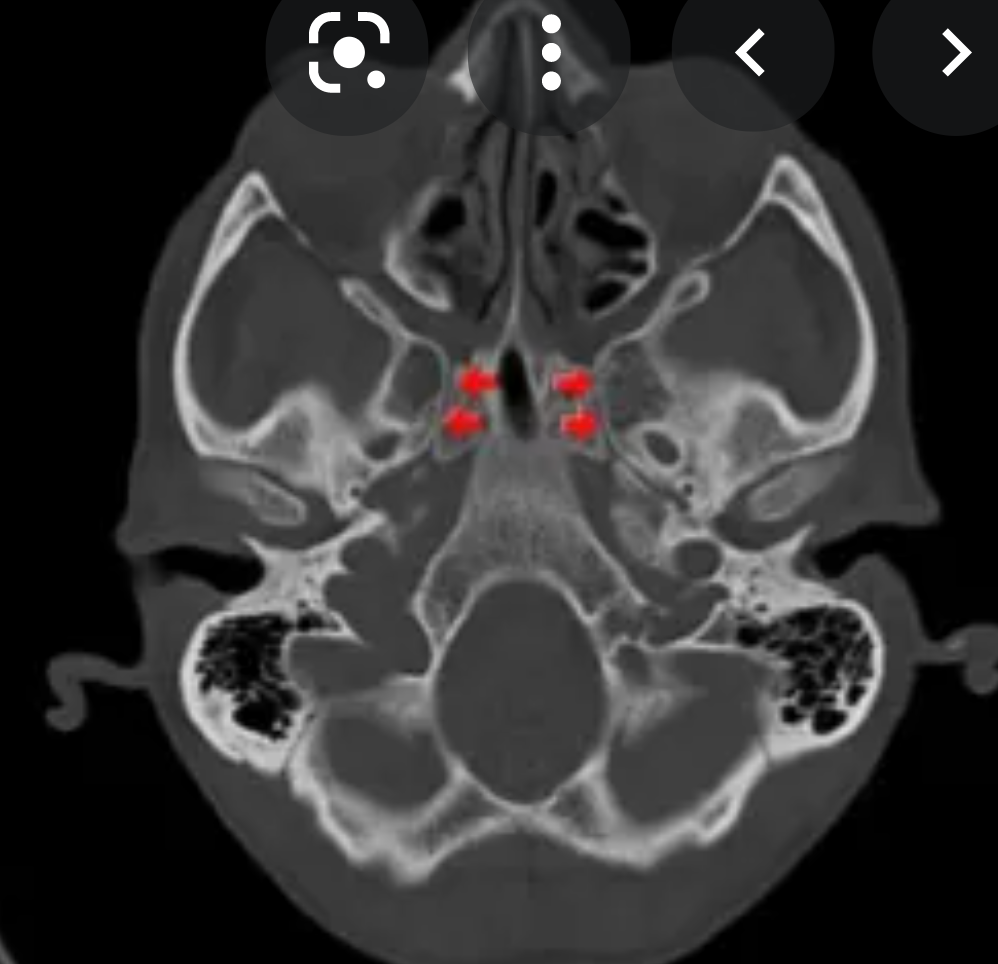

CT

High-density bone deposition within the membranous labyrinth:

mild disease: hazy increase in density within fluid spaces of the membranous labyrinth

moderate disease: focal areas of bony encroachment on fluid spaces of the membranous labyrinth

severe disease: membranous labyrinth completely obliterated by bone replacing fluid spaces

The term otosclerosis is somewhat of a misnomer. Much of the clinical course is characterised by lucent rather than sclerotic bony changes and hence it is more appropriately known as otospongiosis which is a term preferred by many head and neck radiologists.